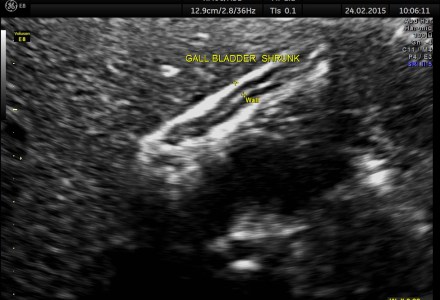

POST FATTY MEAL SCAN IN A SUSPECTED GALL BLADDER DYSFUNCTION